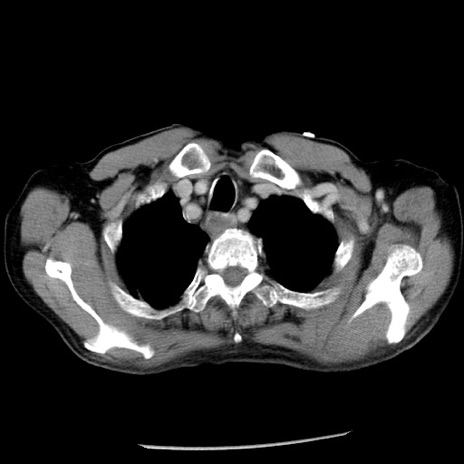

冠状断像

【症例】80歳代男性

【主訴】嘔吐

【現病歴】昨晩2回嘔吐あり、今朝になっても嘔吐あり。来院。

【既往歴】胃潰瘍

【身体所見】意識清明、BT 37.6℃、BP 166/95mmHg、HR 100bpm、SpO2 97%、腹部:平坦・軟、腸蠕動音聴取良好、圧痛なし。

【データ】WBC 21900、CRP 1.46